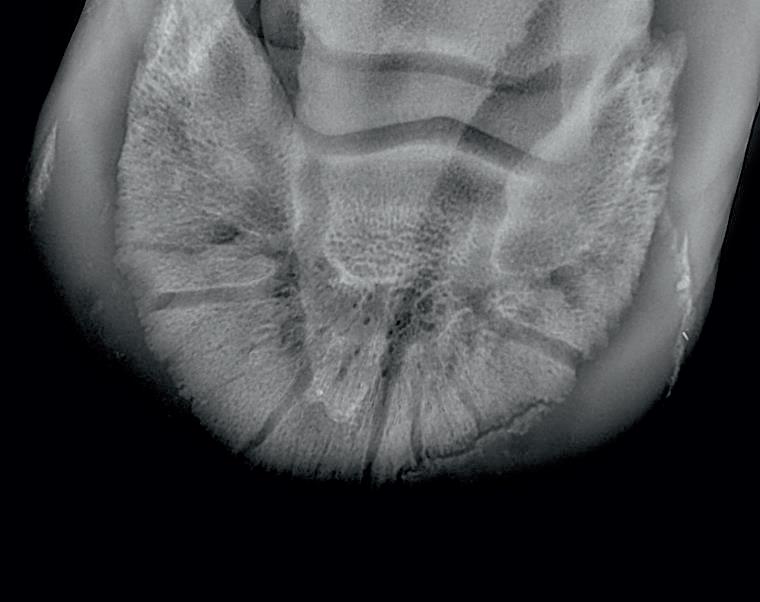

VETERINARY RADIOGRAPHIC REPORT

HORSE: "XXXXXXXX"

DATES OF EXAMINATION: 26TH AUG, 21ST OCT 21 & 17TH NOV '21

PLACE: XXXXXXXXXX FARM

XXXXXXX's left and right front feet were radiographed on 26th Aug, 21st Oct (8 weeks) and again on the 17th Nov '21(12 weeks).

RADIOGRAPHS:

26.08.21: Right Front: Large P3 solar margin fracture evident on medial toe 32.6mm x 4.1mm with approximately 1.4mm separation from parent bone as below left image.

21.10.21: Right Front: Fine residual 4.2mm fracture still evident, approximately 90% resolution

17.11.21: Right Front: Fracture fully resolved

RECOMMENDATIONS:

Radiographic results as of the 17th Nov '21 show total resolution of the original fracture.

XXXXXXX was reshod today utilising off an alloy shoe with a toe clip - inner circumference seated out to avoid any sole pressure.

The horse can return to training. Please do not hesitate to contact me if you have any further queries

COMMENTS:

Solar margin Type IV fractures of this magnitude have well-documented internationally published healing rates of 7 - 12 months. Full resolution of these fractures is rare as most often the fracture fragments are resorbed.

Full resolution in a 3 month period was not anticipated.

The horse was on Bone Gold 3 x scoops fed once per day for this period.